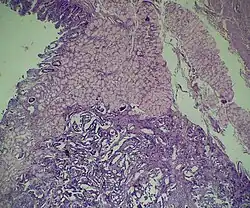

![]() Язвенное образование желудка, по данным биопсии — аденокарцинома | |